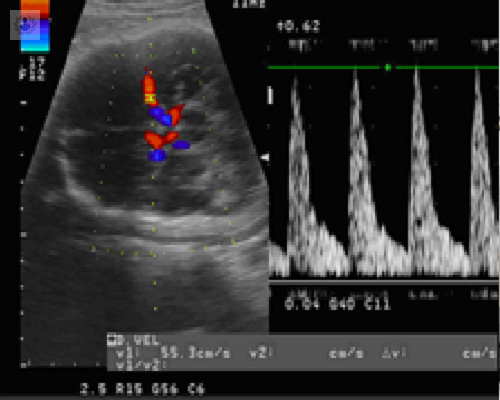

La Ecografía Avanzada es una técnica de diagnóstico por imagen que utiliza tecnología de última generación para evaluar con precisión el estado del feto, la placenta y el entorno uterino durante el embarazo.